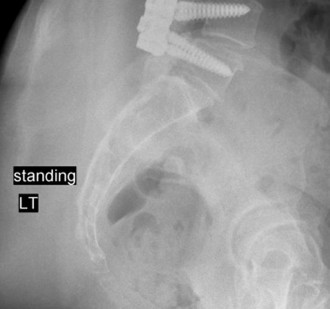

Treatment of an epidural abscess with neurological involvement? The most common organisms causing spinal epidural abscesses? CASE 5 A 62-year-old otherwise healthy woman presents to your clinic with complaints of both chronic low back pain and difficulty ambulating distances secondary to pain radiating into her buttocks and posterior thighs. She reports her pain is relieved with forward flexion. On examination, the patient has a forward flexed posture and 4/5 strength in her bilateral EHLs and left tibialis anterior muscle. She has failed nonoperative treatment including extensive physical therapy and epidural injections. Plain radiographs are shown in Figures 1–11 and 1–12. In addition, an MRI demonstrates significant central stenosis at L4–5 (not shown).

Figure 1–11

Figure 1–12

The best answer is (D). Both decompression (laminectomy) alone and a selective decompression and L4–5 (or L3–5) fusion have a high risk of worsening both the coronal and sagittal plane alignment. The long plate films demonstrate a typical de novo degenerative scoliosis with a coronal curve apex at L2–3, rotatory subluxation at L3–4, a fractional curve at L4–S1, and loss of lumbar lordosis. The most reliable method of treating this patient’s neurogenic claudication, sagittal imbalance, and listhesis is decompression and fusion with instrumentation from the thoracic spine to sacrum.